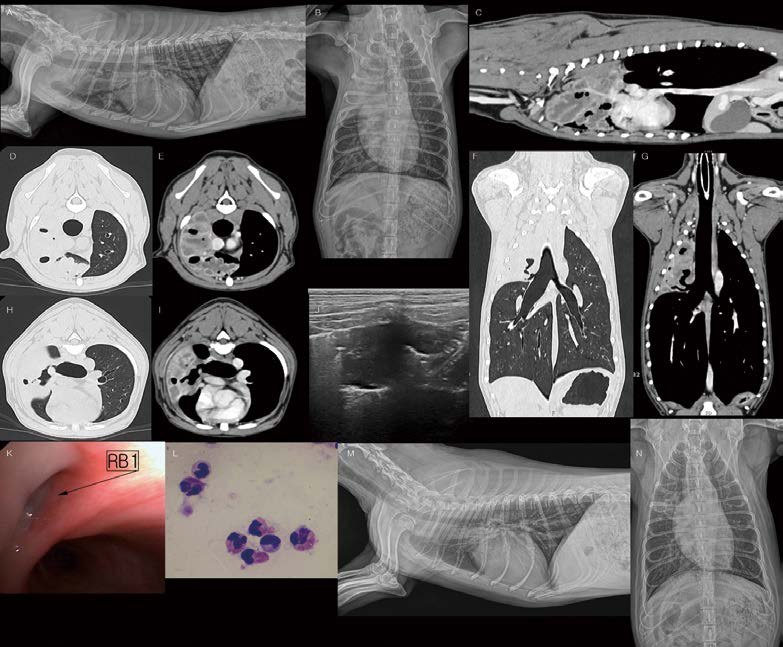

[대한수의사회지 24.png

먼저 흉부초음파(폐초음파)에서 실수하기 쉽거나, 꼭 고려해야 하는 부분이 몇 가지 있습니다. 피하 내 기종, 미만성의 피부 질환, 비만한 환자 등에서 폐가 제대로 스캔되지 않았는데, B line으로 오진하는 경우가 많습니다. 늑골과 늑골 사이에서 lung sliding을 관찰하면서 pleural line, lung periphery, A line 등을 잘 확인해서 판독 가능 여부를 명확히 해야 합니다. 또한 미약한 B line 1개, 짧은 comet tail artifact(B line은 흉막에서 시작해서 수직으로 아래로 뻗는 음영입니다. lung sliding과 함께 움직이며, 한 개의 늑간 사이에 적어도 3개 이상 나타나야 하고, 화면의 끝까지 fading 없이 이어지는 고에코성 라인이어야 임상적 의미가 있다고 보고 있습니다) 등을 병적 상태로 과대 평가하지 않도록 주의해야 합니다(D). 호흡곤란 환자에서 aerophagia로 인해 stomach가 공기로 확장되는 경우가 많은데, 이 때, 확장된 위벽은 얇아져 마치 pleural line처럼 linear하게 보이게 됩니다. 왼쪽 후엽 스캔 시 위 내 공기를 왼쪽 후엽의 confluent B line으로 오진하는 경우도 많습니다.

(A). 폐초음파에서 양쪽 caudodorsal, perihilar, middle, cranial lung field view 모두 8 views 뿐만 아니라 diaphragmatic-hepatic view도 매우 중요합니다. Diaphragmatic hepatic view에서 정상적으로 관찰될 수 있는 curtain sign(B)을 인지하고, 이 부위의 변화 소견은 costophrenic recess, peripheral lung base와 관련된 pulmonary pathology를 발견하는데 유용합니다(C, pleural effusion).

<※증례 ①>

13살 수컷 Cocker spaniel이 기침, 호흡곤란으로 내원하였습니다. CRP 172.7 (0 15mg/dl ~) 확인되었고, 흉부방사선 검사에서 양쪽 전엽의 밀도가 약간 증가(특히 우측)되어 보입니다(A, B). 그러나 비만한 체형, 둥근 심음영, 최대 흡기 촬영이 되지 않은 점, Skin fold artifact 등으로 인해 좀 더 세밀한 판독은 어렵습니다. 폐초음파 검사를 실시했을 때, 왼쪽 전엽은 collapse되어 관찰되며(C), 오른쪽 전엽은 shred sign을 동반한 폐 침윤 소견이 일정 영역 이상 관찰됩니다(D). 오른쪽 전엽 주변 후방으로 소량의 B line이 관찰됩니다(E). C와 같은 lung collapse(atelectasis)는 폐엽 volume이 감소하고, 균질한 contour를 보이며, dynamic air bronchogram 없이 static air bronchogram 또는 공기 음영이 소실된 parallel-running bright lines만 관찰되게 됩니다.

이 환자에서 좌측 전엽은 기존 폐렴 병력으로 인한 atelectasis 가능성이 고려됩니다. D의 소견은 병적인 폐침윤 영역과 정상 폐 공기 음영의 irregular interface, 즉 shred sign을 동반한 폐렴의 전형적인 영상입니다. 실시간으로 보면 dynamic air bronchogram이 관찰됩니다. 이렇게 현재 진행형인 폐의 병적 변화 주변으로는 focal parapneumonic pulmonary edema도 함께 관찰될 수 있습니다(E). 다만, shred line으로부터 우연히 발생하는 ring-down artifact와 parapneumonic pulmonary edema는 감별해야 합니다. 이렇게 폐초음파는 병변의 양상을 파악하고, chronicity, severity 정도를 판단함으로써, 환자의 치료 방향을 제시하고, 개선/악화/변화 없음 등의 모니터링에 유용하게 사용될 수 있습니다. 환자는 보호자님의 요청으로 추가적인 검사 없이 일반적인 폐렴에 준한 치료를 진행하였고, 대부분 개선되었습니다.